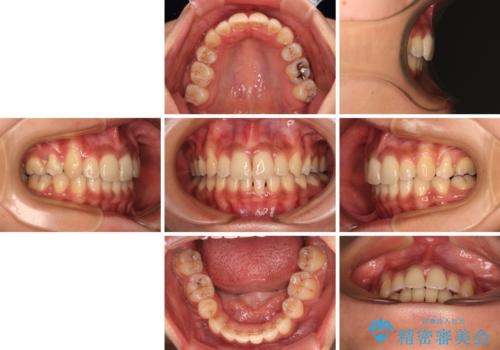

- 八重歯と上下前歯のでこぼこを気にして来院された患者様です。

上下前歯部叢生のスペース獲得のため、上下顎左右小臼歯各1歯(計4本)を抜歯して、ワイヤー装置にて矯正治療を行うこととしました。

上下の正中位置が大きくずれていたため、上下正中が合わないまま終了することが予想されましたが、思っていた以上にスムーズに歯が移動し、満足いただける仕上がりとなりました。